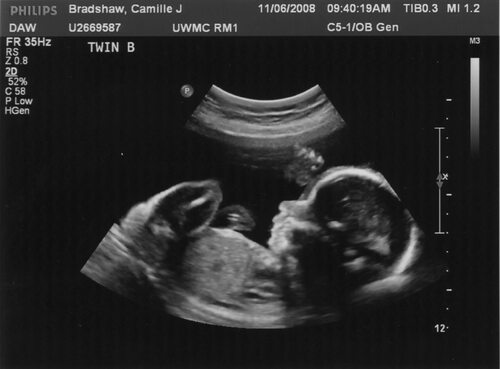

УЗИ с фотографией плода – это процедура, которая позволяет получить детальные изображения плода внутри матки. Ультразвуковое исследование (УЗИ) является одним из основных методов диагностики во время беременности.

УЗИ с фотографией плода проводится специалистом врачом-ультразвуковым диагностом. При помощи специального аппарата, который излучает высокочастотные звуковые волны, врач получает изображение плода на экране. Во время процедуры мать лежит на специальном кресле, а врач наносит гель на живот, чтобы облегчить скольжение датчика и улучшить качество изображения.

УЗИ с фотографией плода является важным методом для оценки здоровья и развития ребенка в утробе матери. С его помощью можно выявить возможные аномалии развития, контролировать рост и вес плода, а также определить пол ребенка. Кроме того, ультразвуковое исследование позволяет родителям увидеть своего малыша и создать первые фотографии для будущих воспоминаний.